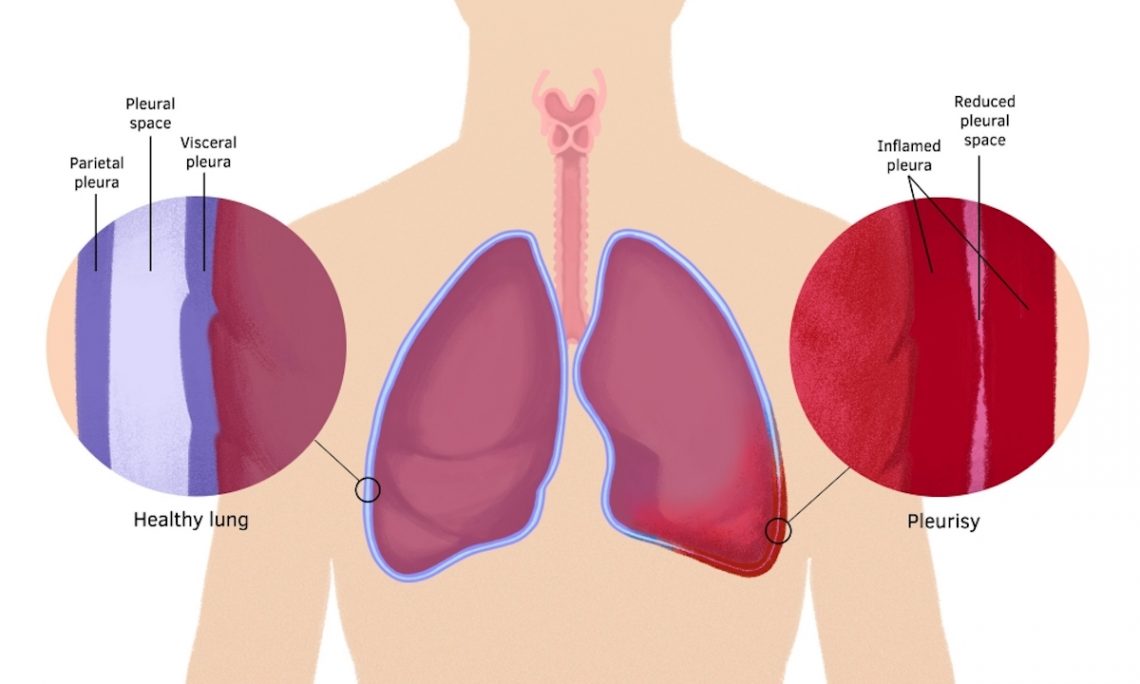

Can Pleural Plaques Cause Pain .  pleural plaques are distinct from dpt, which consists of extensive fibrosis of the visceral pleura, often.  also called pleuritis, pleurisy causes sharp chest pain (pleuritic pain) that worsens during breathing.  pleuritic chest pain is characterized by sudden and intense sharp, stabbing, or burning pain in the chest when inhaling and exhaling. many persons, often those who have only had brief exposure, develop pleural plaques.  an injury, inflammation , or infection can cause the blood or air to build up in the pleural space and lead to a. One pleural layer of tissue wraps around.  pleural plaques can be a sign of exposure to asbestos, which can increase someone’s risk of developing fatal. pleural plaques are areas of tissue that become thickened in the lining of the lungs. They are generally seen as a marker of past.

pleuritic chest pain is characterized by sudden and intense sharp, stabbing, or burning pain in the chest when inhaling and exhaling. many persons, often those who have only had brief exposure, develop pleural plaques. pleural plaques are areas of tissue that become thickened in the lining of the lungs. They are generally seen as a marker of past. One pleural layer of tissue wraps around.  an injury, inflammation , or infection can cause the blood or air to build up in the pleural space and lead to a.  also called pleuritis, pleurisy causes sharp chest pain (pleuritic pain) that worsens during breathing.  pleural plaques are distinct from dpt, which consists of extensive fibrosis of the visceral pleura, often.  pleural plaques can be a sign of exposure to asbestos, which can increase someone’s risk of developing fatal.

Can Pleural Plaques Cause Pain  pleural plaques are areas of tissue that become thickened in the lining of the lungs.  an injury, inflammation , or infection can cause the blood or air to build up in the pleural space and lead to a. One pleural layer of tissue wraps around. pleural plaques are areas of tissue that become thickened in the lining of the lungs.  also called pleuritis, pleurisy causes sharp chest pain (pleuritic pain) that worsens during breathing.  pleuritic chest pain is characterized by sudden and intense sharp, stabbing, or burning pain in the chest when inhaling and exhaling.  pleural plaques are distinct from dpt, which consists of extensive fibrosis of the visceral pleura, often. many persons, often those who have only had brief exposure, develop pleural plaques. They are generally seen as a marker of past.  pleural plaques can be a sign of exposure to asbestos, which can increase someone’s risk of developing fatal.